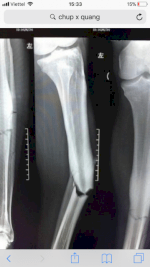

Phim X Quang Drystar Dt2B Cỡ 14X17 Inch (35Cm X 43Cm), Phim Chụp Ct, Mri

0435 *** ***

Hà Nội

>1 năm

Thu Mua Phim Chụp X-Quang , Ct, Mri Đã Qua Sử Dụng.

0985 *** ***

Toàn quốc

>1 năm